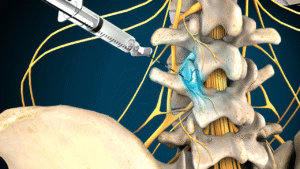

- Minimally invasive procedures

Back pain

Il dolore lombare è una condizione molto frequente. Può avere diverse cause, come problemi muscolari, articolari o discali, e spesso limita le attività quotidiane.